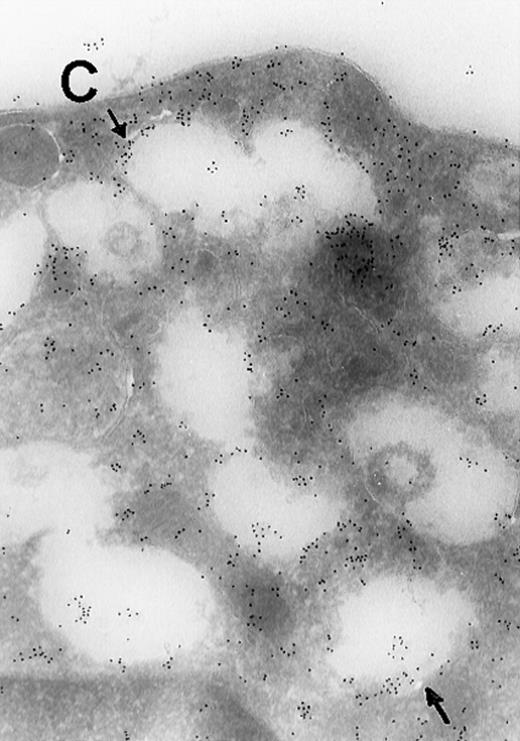

Immunogold Electron Microscopic assays (performed as described before)9.

(A) Ultrathin frozen sections of rat platelets immunolabeled with antibodies to ERK (magnification ×45 000). (B) Well-developed demarcation membranes in a rat (Wistar), TPO-treated megakaryocyte7 9 immunostained with an antibody to Mst1 (magnification ×48 000), or (C) with an antibody to ERK, which recognizes ERK1 and ERK2 (magnification ×65 400). The arrows point to the demarcation membranes. The Mst1 antiserum (gift of Dr Jonathan Chernoff, Fox Chase Cancer Center, Philadelphia, PA) and anti-ERK2 (K-23) (Santa Cruz Biotechnology, Santa Cruz, CA) or TR2, anti-ERK (gift of Michael Weber, University of Virginia Medical School) were diluted 1:10.

In view of these reports, we determined the cellular localization of MAP kinase in megakaryocytes, with a particular attention to the platelet-yielding demarcation membranes.7As a control, we determined the localization of another TPO-upregulated serine/threonine kinase, Mst1.8 Our current Electron Microscopic (EM) studies, performed as we described before,9 reveal that a significant fraction of MAP kinase, but none of Mst1, localizes to the demarcation membranes. In resting platelets, MAP kinase is found in a cluster pattern associated with the plasma membrane (which is believed to originate from the megakaryocytic demarcation membranes),7 as well as over electron-dense cytoplasmic domains (Figure). In view of our finding that MAP kinase is localized to the demarcation membranes in megakaryocytes, it is of interest to note that this kinase was also shown to be localized in Golgi membranes and involved in their fragmentation during mitosis in a microtubule-dependent manner.10 Platelet fragmentation likely involves the cytoskeleton, and perhaps MAP kinases are also involved in this process.